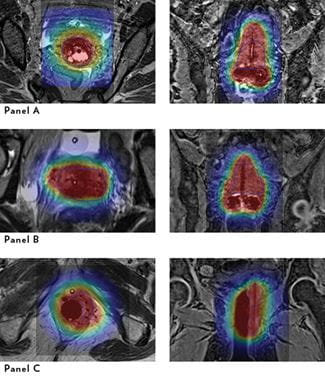

Once the parameters of the tumor are known from the MRI, radiation sources can be introduced using special applicators and needles that enable Cooper and other radiation oncologists to “tailor” or “sculpt” the dose of the radiation to match the contours of the tumor (Image below).

Magnetic Resonance Planning Images for High-Dose-Rate Brachytherapy

Axial T2 (left) and coronal T1 (right) slices of magnetic resonance planning images for high-dose-rate brachytherapy are provided for a single patient in each of the panels. The disease volume targeted for treatment is outlined in blue. For all images, the overlaid color wash represents the dose given during treatment, with the red area receiving the prescription dose.

Panel A. Tandem and ovoids for locally advanced cervical cancer. On the axial slice, the tandem is visible centrally in the target volume. On the coronal slice, the tandem can be seen centrally in the uterus with the ovoids placed on either side of the cervical os.

Panel B. Tandem and ovoids plus five needles for locally advanced cervical cancer. The needles are used to extend the dose asymmetrically beyond the central tandem and custom shape the dose distribution to the target volume.

Panel C. Interstitial implant with Syed applicator consisting of a vaginal obturator and 12 surrounding needles in and around the obturator for a uterine cancer vaginal recurrence. The central needles in the obturator provide a symmetric distribution of dose, while the needles in the tissue to the left of the obturator provide channels that are used to extend the dose asymmetrically and custom shape the dose distribution to the target volume.